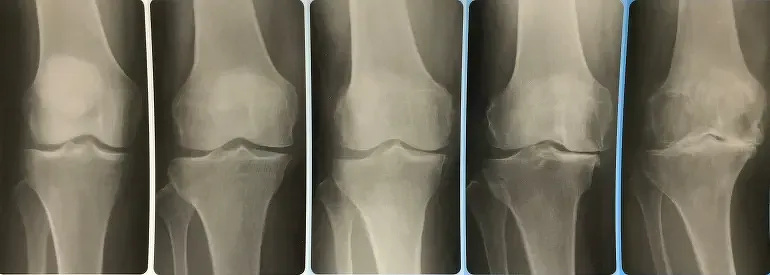

ここでは膝関節に発生する「変形性膝関節症」の焦点を当て、医療機関で行われる膝関節の手術方法などをご紹介します。

〈変形性膝関節症の疫学〉

変形性関節症の患者さんの人数は、年齢とともに増加します。60歳以上の人口の80%以上で、膝関節・肘関節・股関節・背骨に、変形性関節症の所見をみとめるという報告もあります。

膝関節の場合は「変形性膝関節症(へんけいせいひざかんせつしょう、へんけいせいしつかんせつしょう)」、股関節の場合は「変形性股関節症(へんけいせいこかんせつしょう)」と呼ばれます。とくに変形性膝関節症の患者は多く、自覚症状がある患者数は1000万人、自覚症状がない(レントゲン画像上の変化のみ)人数も合わせると3000万人の患者がいるといわれます。患者の性別は、女性のほうが男性よりも1.5〜2倍多く認めます。一方、変形性股関節症の患者は120万〜510万人いるとされ、9割が女性です。